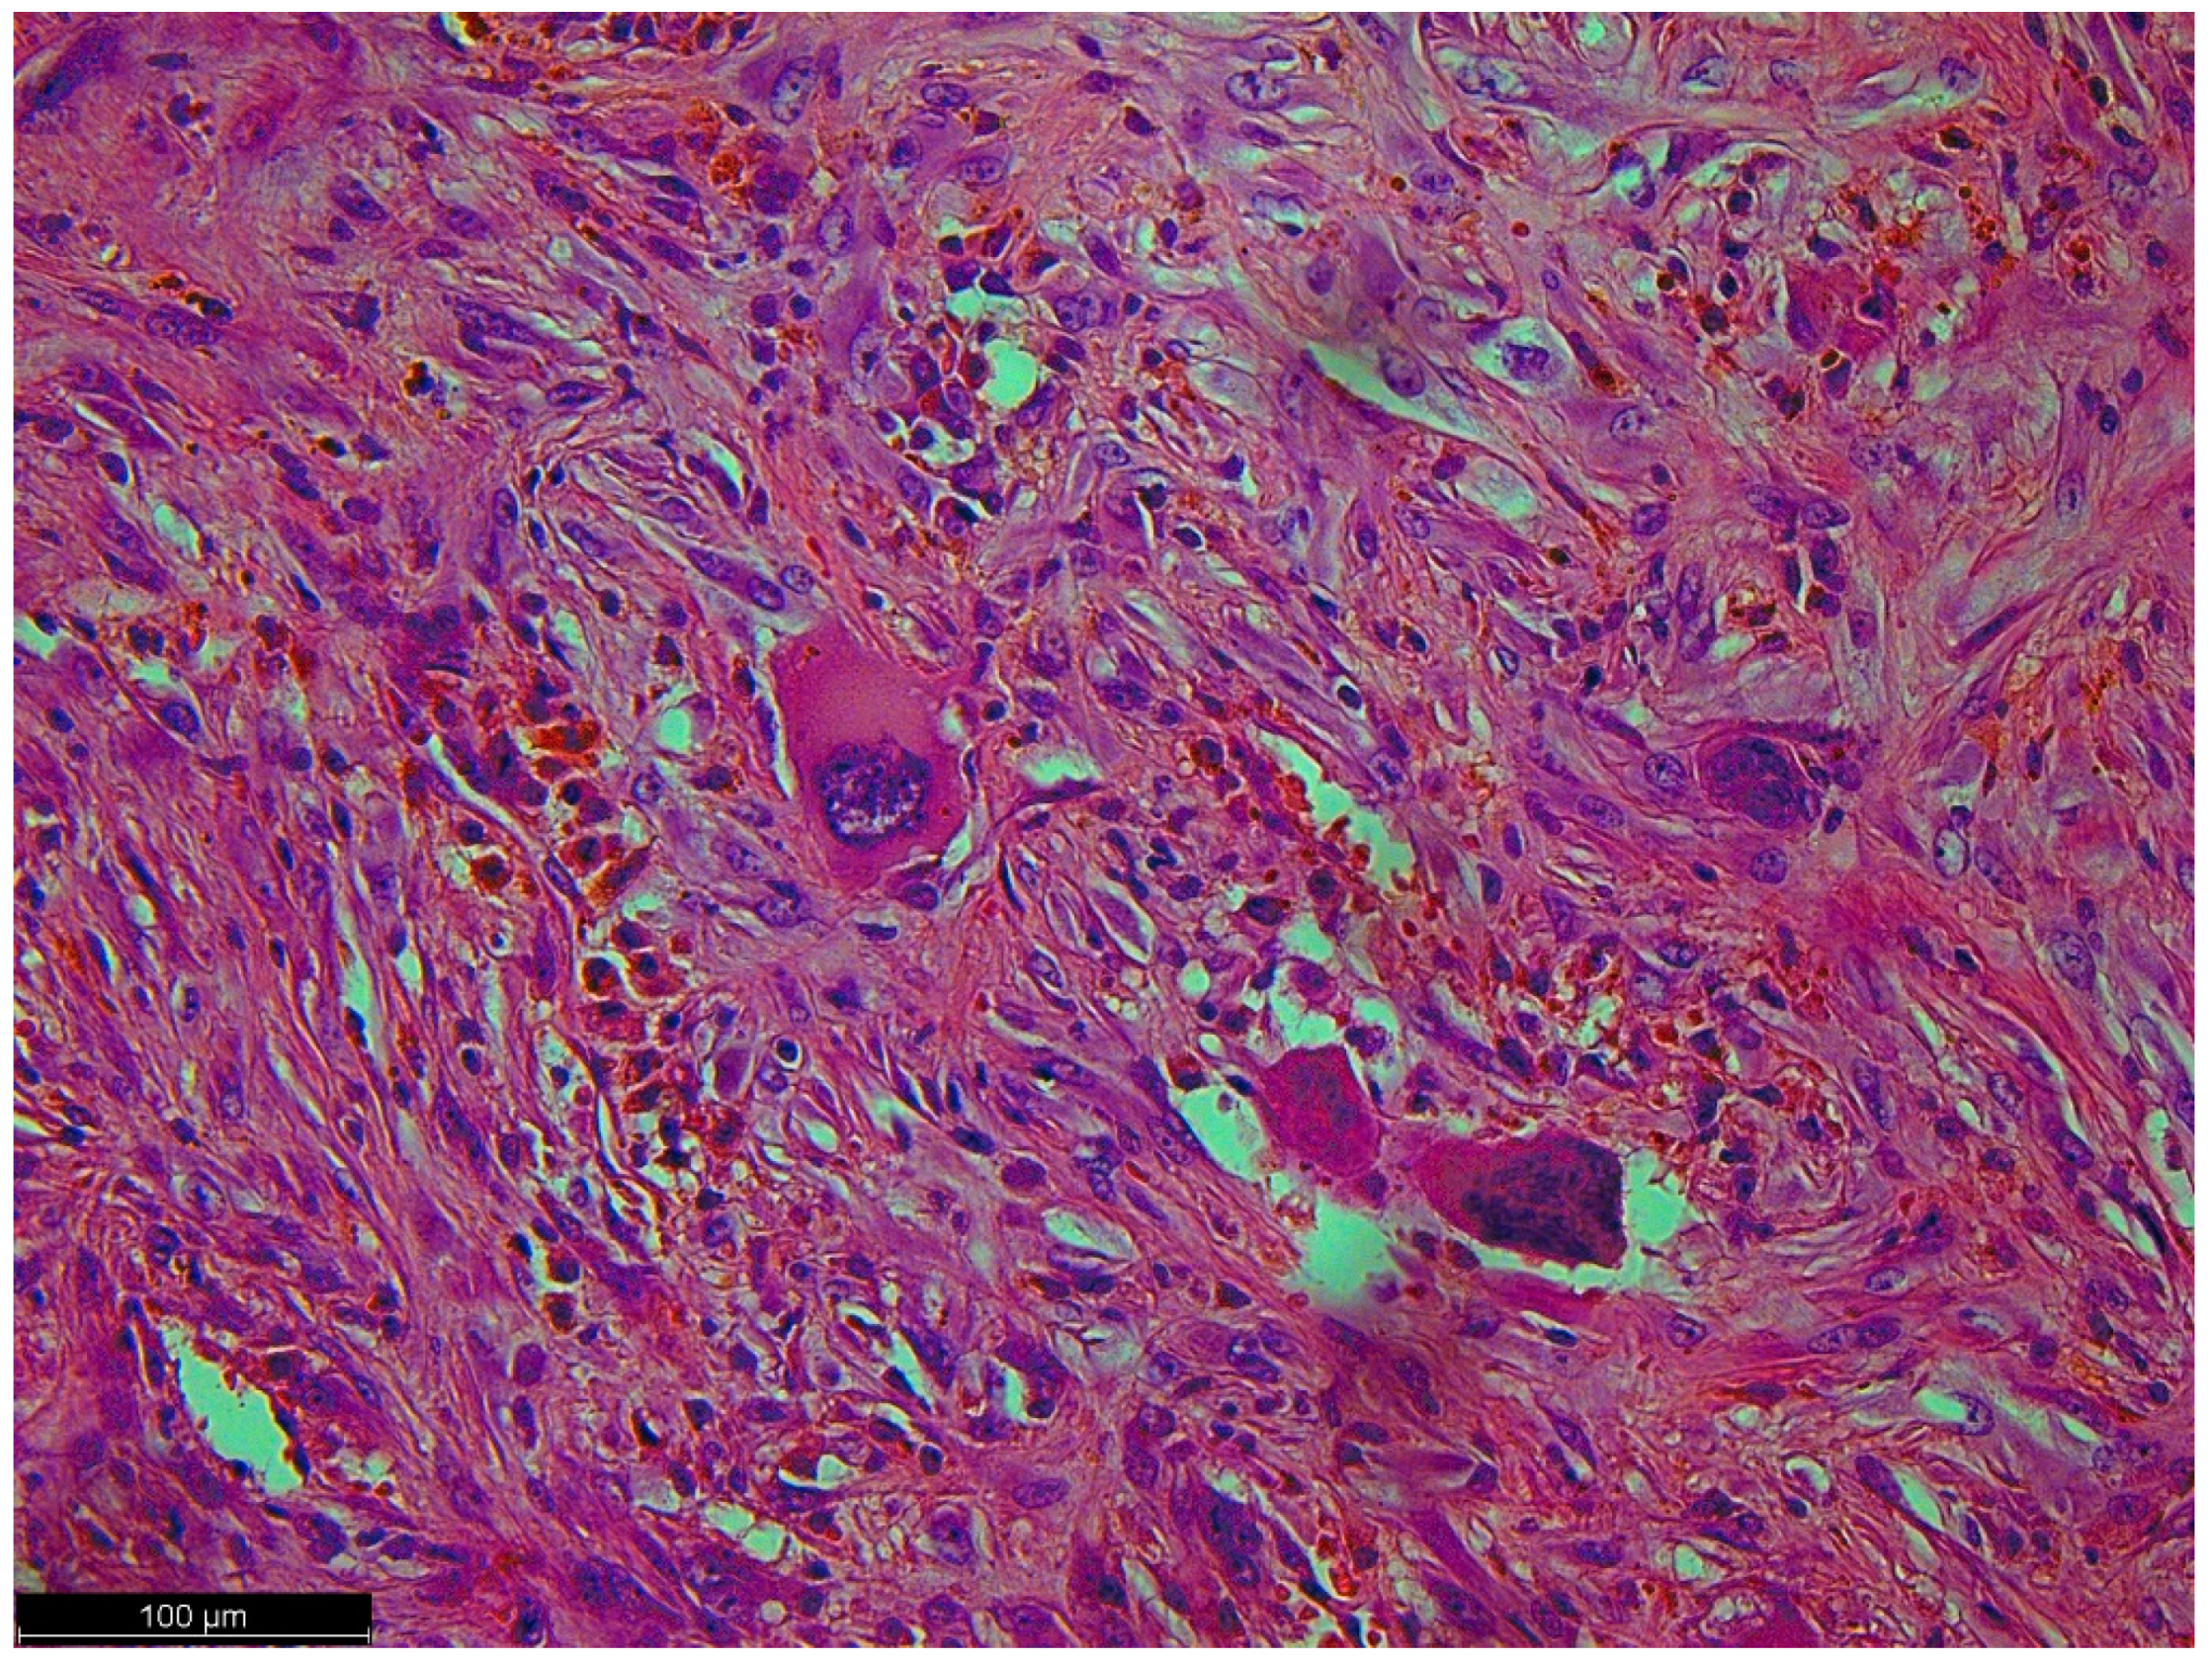

As a result of macroscopic histopathologic examination, the surgical material was described as a solid, polycyclic, cream-colored tumor, partly with a cyst. The cystic part was filled with yellow fluid. In addition, hemorrhagic changes and massive calcifications were observed within the tumor. Histopathologic examination described cytologic atypia as high grade with mitotic activity: 10/1734 mm2 and no signs of necrosis. Immunohistochemistry (IHC) results were: MDM2 (+/−) focal, CDK4 (+/−), desmin (−), myogenin (−), caldesmon (−). Numerous multinucleated giant cells with osteoclast morphology were mainly located around the hemorrhage and ossification. Amplification of the MDM2 gene was detected via fluorescence in situ hybridization (FISH). The final diagnosis was described as dedifferentiated liposarcoma FNCLCC (Fédération Nationale de Centres de Lutte Contre le Cancer), G2 (Grade 2) with osteosarcomatous differentiation, pT2 N0 (Figure 4, Figure 5 and Figure 6) [13].

Figure 6.

Pleomorphic cells with high-grade atypia; they did not show typical differentiation. There were no lipoblasts or remnants of well-differentiated liposarcoma (the precursor to this tumor) because a dedifferentiated component had overgrown it.